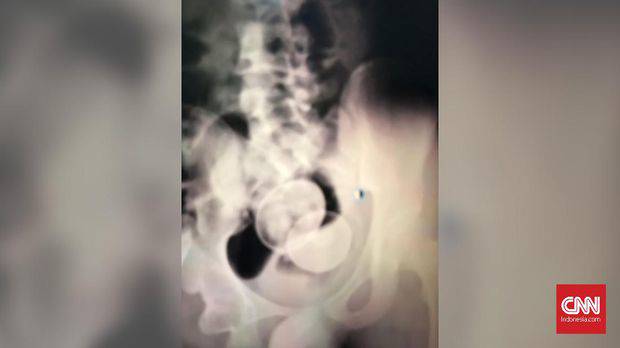

Setibanya di RS Syech Yusuf, Akmal langsung menjalani perawatan intensif, ia bahkan sempat di-rontgen untuk mengetahui jumlah telur yang ada di dalam tubuh Akmal.

"Dari foto Ronsen-nya, kita lihat tadi ada dua biji telur," ucap Ruslim.

Foto rontgen tubuh Akmal. (CNN Indonesia/Fauzan)